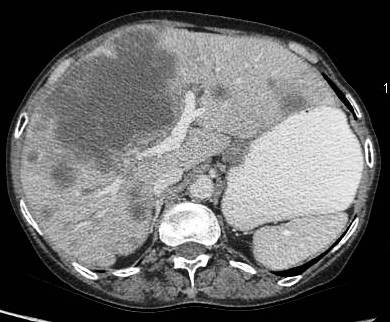

Common patterns of carcinoma gallbladder

Three patterns have been described on ultrasonography (US). The gallbladder fossa is replaced by a heterogeneous mass (figure 1) with internal areas of necrosis; or there may be diffuse, irregular, and asymmetrical wall thickening (Figure 2); or less commonly, a polypoidal, fungating intra-luminal mass is seen. Correct preoperative diagnosis has improved considerably with the use of newer imaging techniques [6-8]. Majority of cases when diagnosed, are no longer resectable (Figure 3) [9-11].

Figure 3: large polypoidal fungating gallbladder mass with gross invasion of liver parenchyma. Hepato-duodenal ligament invaded. Left lobe shows discrete secondaries.